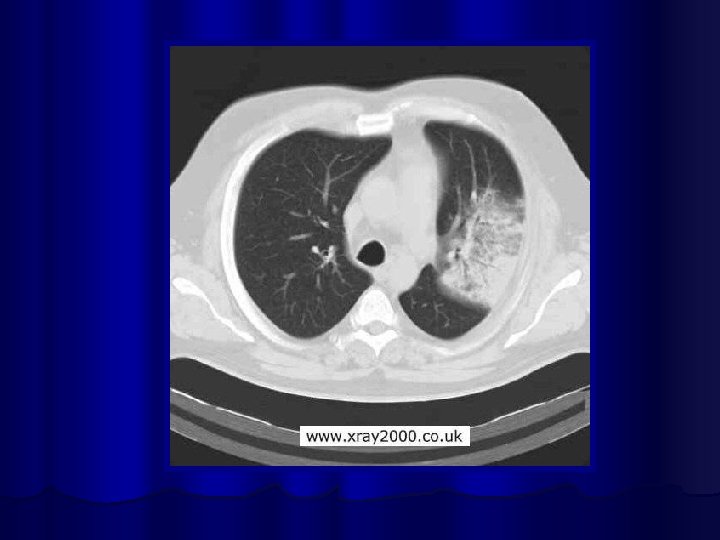

Рентгенологическая картина ВП l Основной рентгенологический признак ВП - локальное снижение воздушности легочной ткани (инфильтрация) за счет накопления воспалительного экссудата в респираторных отделах. l Рентгенологическая и КТ картина ВП определяется типом инфильтрации легочной ткани и стадией воспалительного процесса.

Альвеолярный тип инфильтрации (консолидация) при пневмонии Наблюдается при заполнении воспалительным экссудатом воздухосодержащих альвеол, альвеолярных мешков, альвеолярных ходов и респираторных бронхиол. l Особенности: l средняя интенсивность тени уплотненного участка легкого при рентгенографии l и тканевая плотность при КТ l видимость в зоне уплотнения воздушных просветов бронхов (симптом воздушной бронхографии). l Определяется как плевропневмония. l Чаще встречается при инфицировании бактериальными возбудителями, особенно пневмококком. l

Интерстициальный тип инфильтрации (матовое стекло) Наблюдается при заполнении воспалительным экссудатом межальвеолярных пространств. l Особенности: l низкая (малая) интенсивность тени уплотненного участка при рентгенографии l «симптом матового стекла» при высокоразрешающей КТ легких l видимость стенок бронхов и элементов сосудистого рисунка в зоне инфильтрации. l Определяются как интерстициальные. l Не имеют отчетливой физикальной симптоматики, и могут выявляться при обычной рентгенографии. l Чаще возникают при небактериальных пневмониях. l

Показания для проведения КТ Клиническая симптоматика пневмонии + l отсутствие изменений на рентгеновских снимках или их косвенный характер (например, изменение легочного рисунка) l наличие нетипичных для пневмонии изменений. l Рецидивирующая пневмония, при которой инфильтративные изменения возникают в той же доле (сегменте), что и в предшествующем эпизоде заболевания. l Затяжная пневмония, при которой длительность существования инфильтративных изменений в легочной ткани превышает один месяц. l